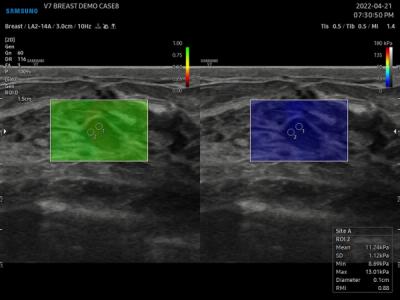

Πρωτοποριακή Ελαστογραφία Shear Wave

Ιδιαίτερα σημαντική είναι η ενσωμάτωση της πλέον σύγχρονης μεθόδου ελαστογραφίας, S-Shearwave Imaging™. Αυτή η μη επεμβατική τεχνική μας επιτρέπει να μετράμε ποσοτικά τη σκληρότητα των ιστών, παρέχοντας κρίσιμες πληροφορίες για τη διάγνωση και παρακολούθηση παθήσεων του ήπατος, του μαστού, του θυρεοειδή και άλλων οργάνων, συχνά αντικαθιστώντας την ανάγκη για βιοψία.